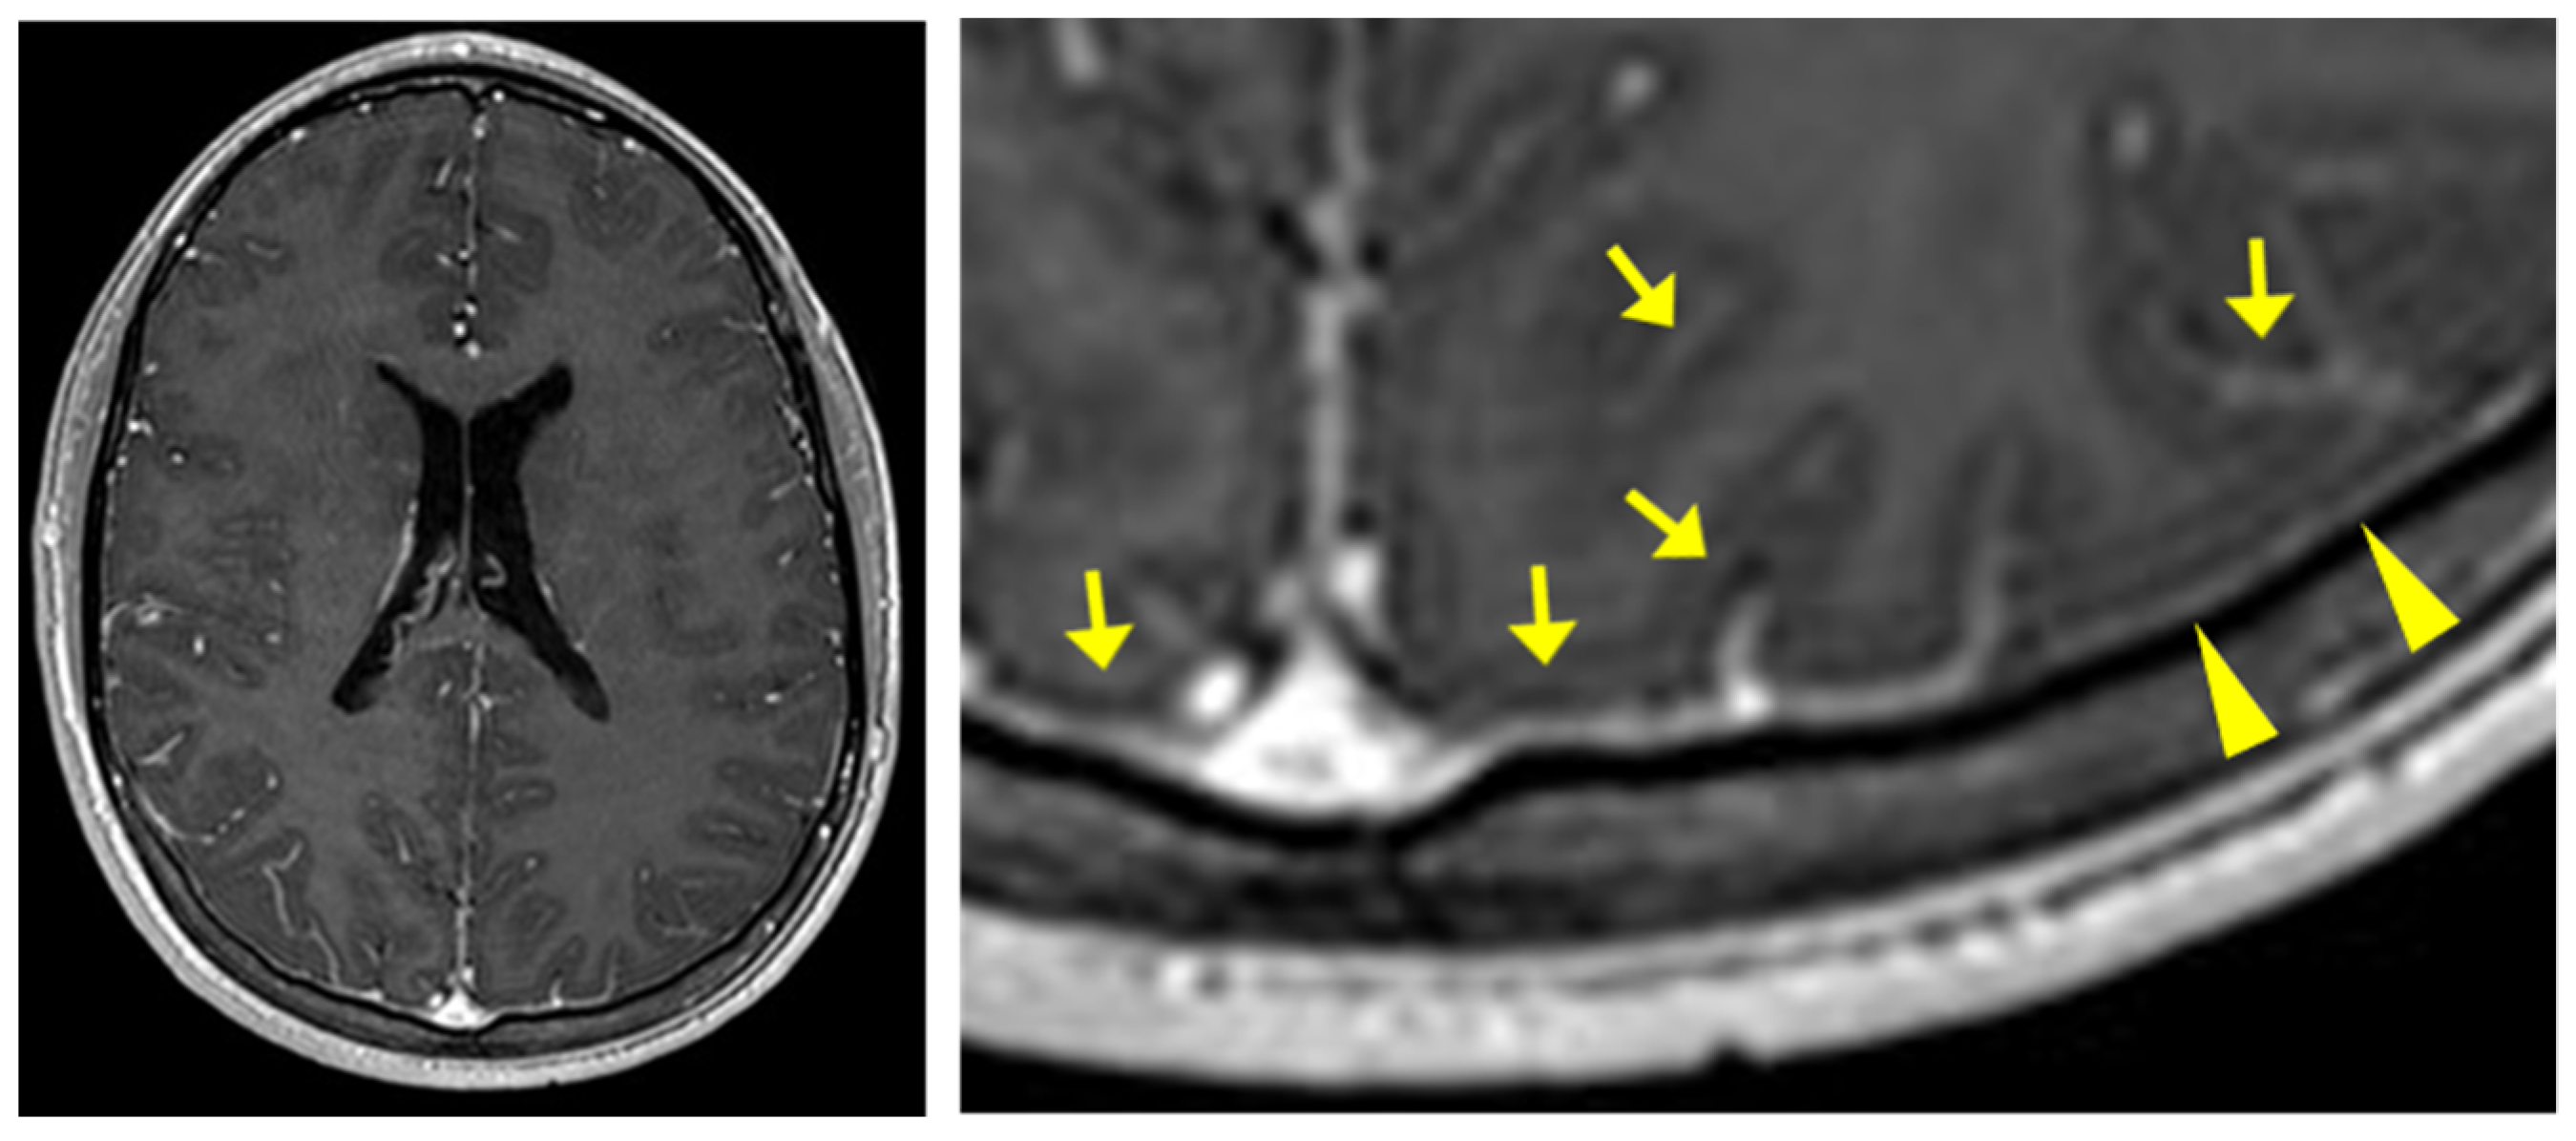

| cMRI | normal | subtle leptomeningeal enhancement | normal | intracranial hypertension | normal | subtle leptomeningeal enhancement |